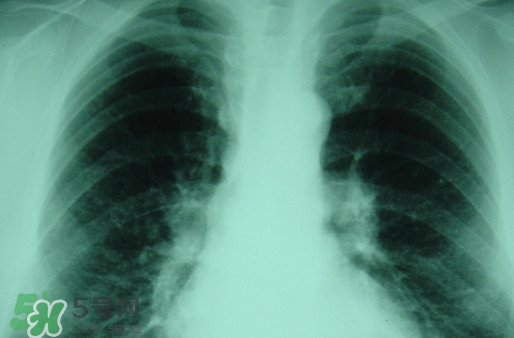

對(duì)于塵肺病,很多人都是陌生而又熟悉,因?yàn)槠渚褪且环N人體肺部滿身灰塵的病癥,一般從事煤礦或是珠寶打磨行業(yè)人群患病率高。那么,塵肺病能治愈嗎?塵肺病能活多久?

塵肺病受制于現(xiàn)行的醫(yī)療技術(shù),目前塵肺病是無(wú)法徹底治好的。

塵肺病屬于不可逆疾病,一定要及時(shí)及早治療!